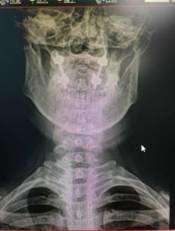

颈椎前路减压融合内固定术治疗脊髓型颈椎病

优点:直接减压,彻底解决突出问题,稳定。

颈椎后开门Arch钛板固定术治疗颈椎后纵韧带骨化症

优点:减压范围广,疗效缺切,保留颈椎的活动度。

寰枢椎固定融合术治疗颅底凹陷、齿状突骨折等

特点:手术风险高。